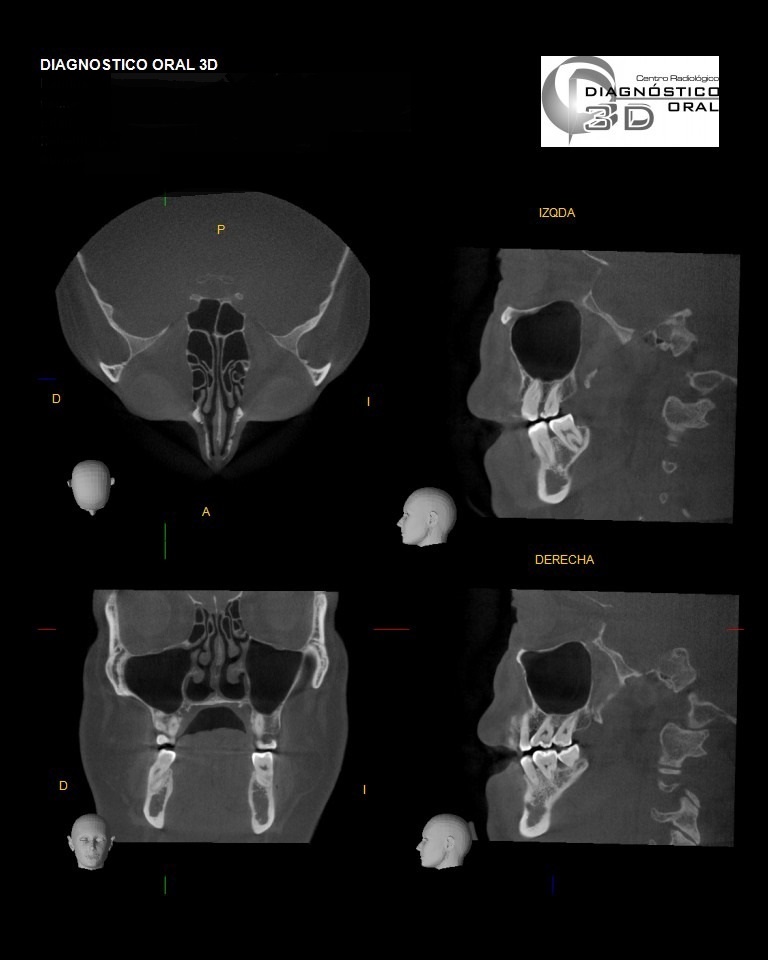

El Centro Radiológico Diagnóstico Oral 3D, es una empresa antioqueña que ofrece a sus pacientes desde el año 2009, tecnología de vanguardia en radiografías tridimensionales con calidad fotográfica. Las posibilidades para mejorar la eficacia en los diagnósticos bucales son evidentes, también lo son las posibilidades de manipulación de imagen. El sistema de imágenes en 3D ofrece detalles sin precedentes, convirtiéndola en la opción idónea para la mayoría de aplicaciones odontológicas, incluyendo implantes, tratamiento de conductos, ortodoncia, odontopediatría, periodoncia y cirugía

El mayor beneficiado con el uso de esta tecnología es el paciente, el cual podrá ser evaluado en todas sus dimensiones con una baja dosis de radiación, con un costo accesible y sin contaminar  el medio ambiente. Dependiendo de la necesidad del paciente, hay varios tipos de tomografías y los especialistas en el área odontológica hacen uso de ellas según su especialidad.

Evaluación de patologías dentales y maxilofaciales

Planificación de tratamientos ortodónticos y ortognáticos

Evaluación pre y postoperatoria de cirugías maxilofaciales